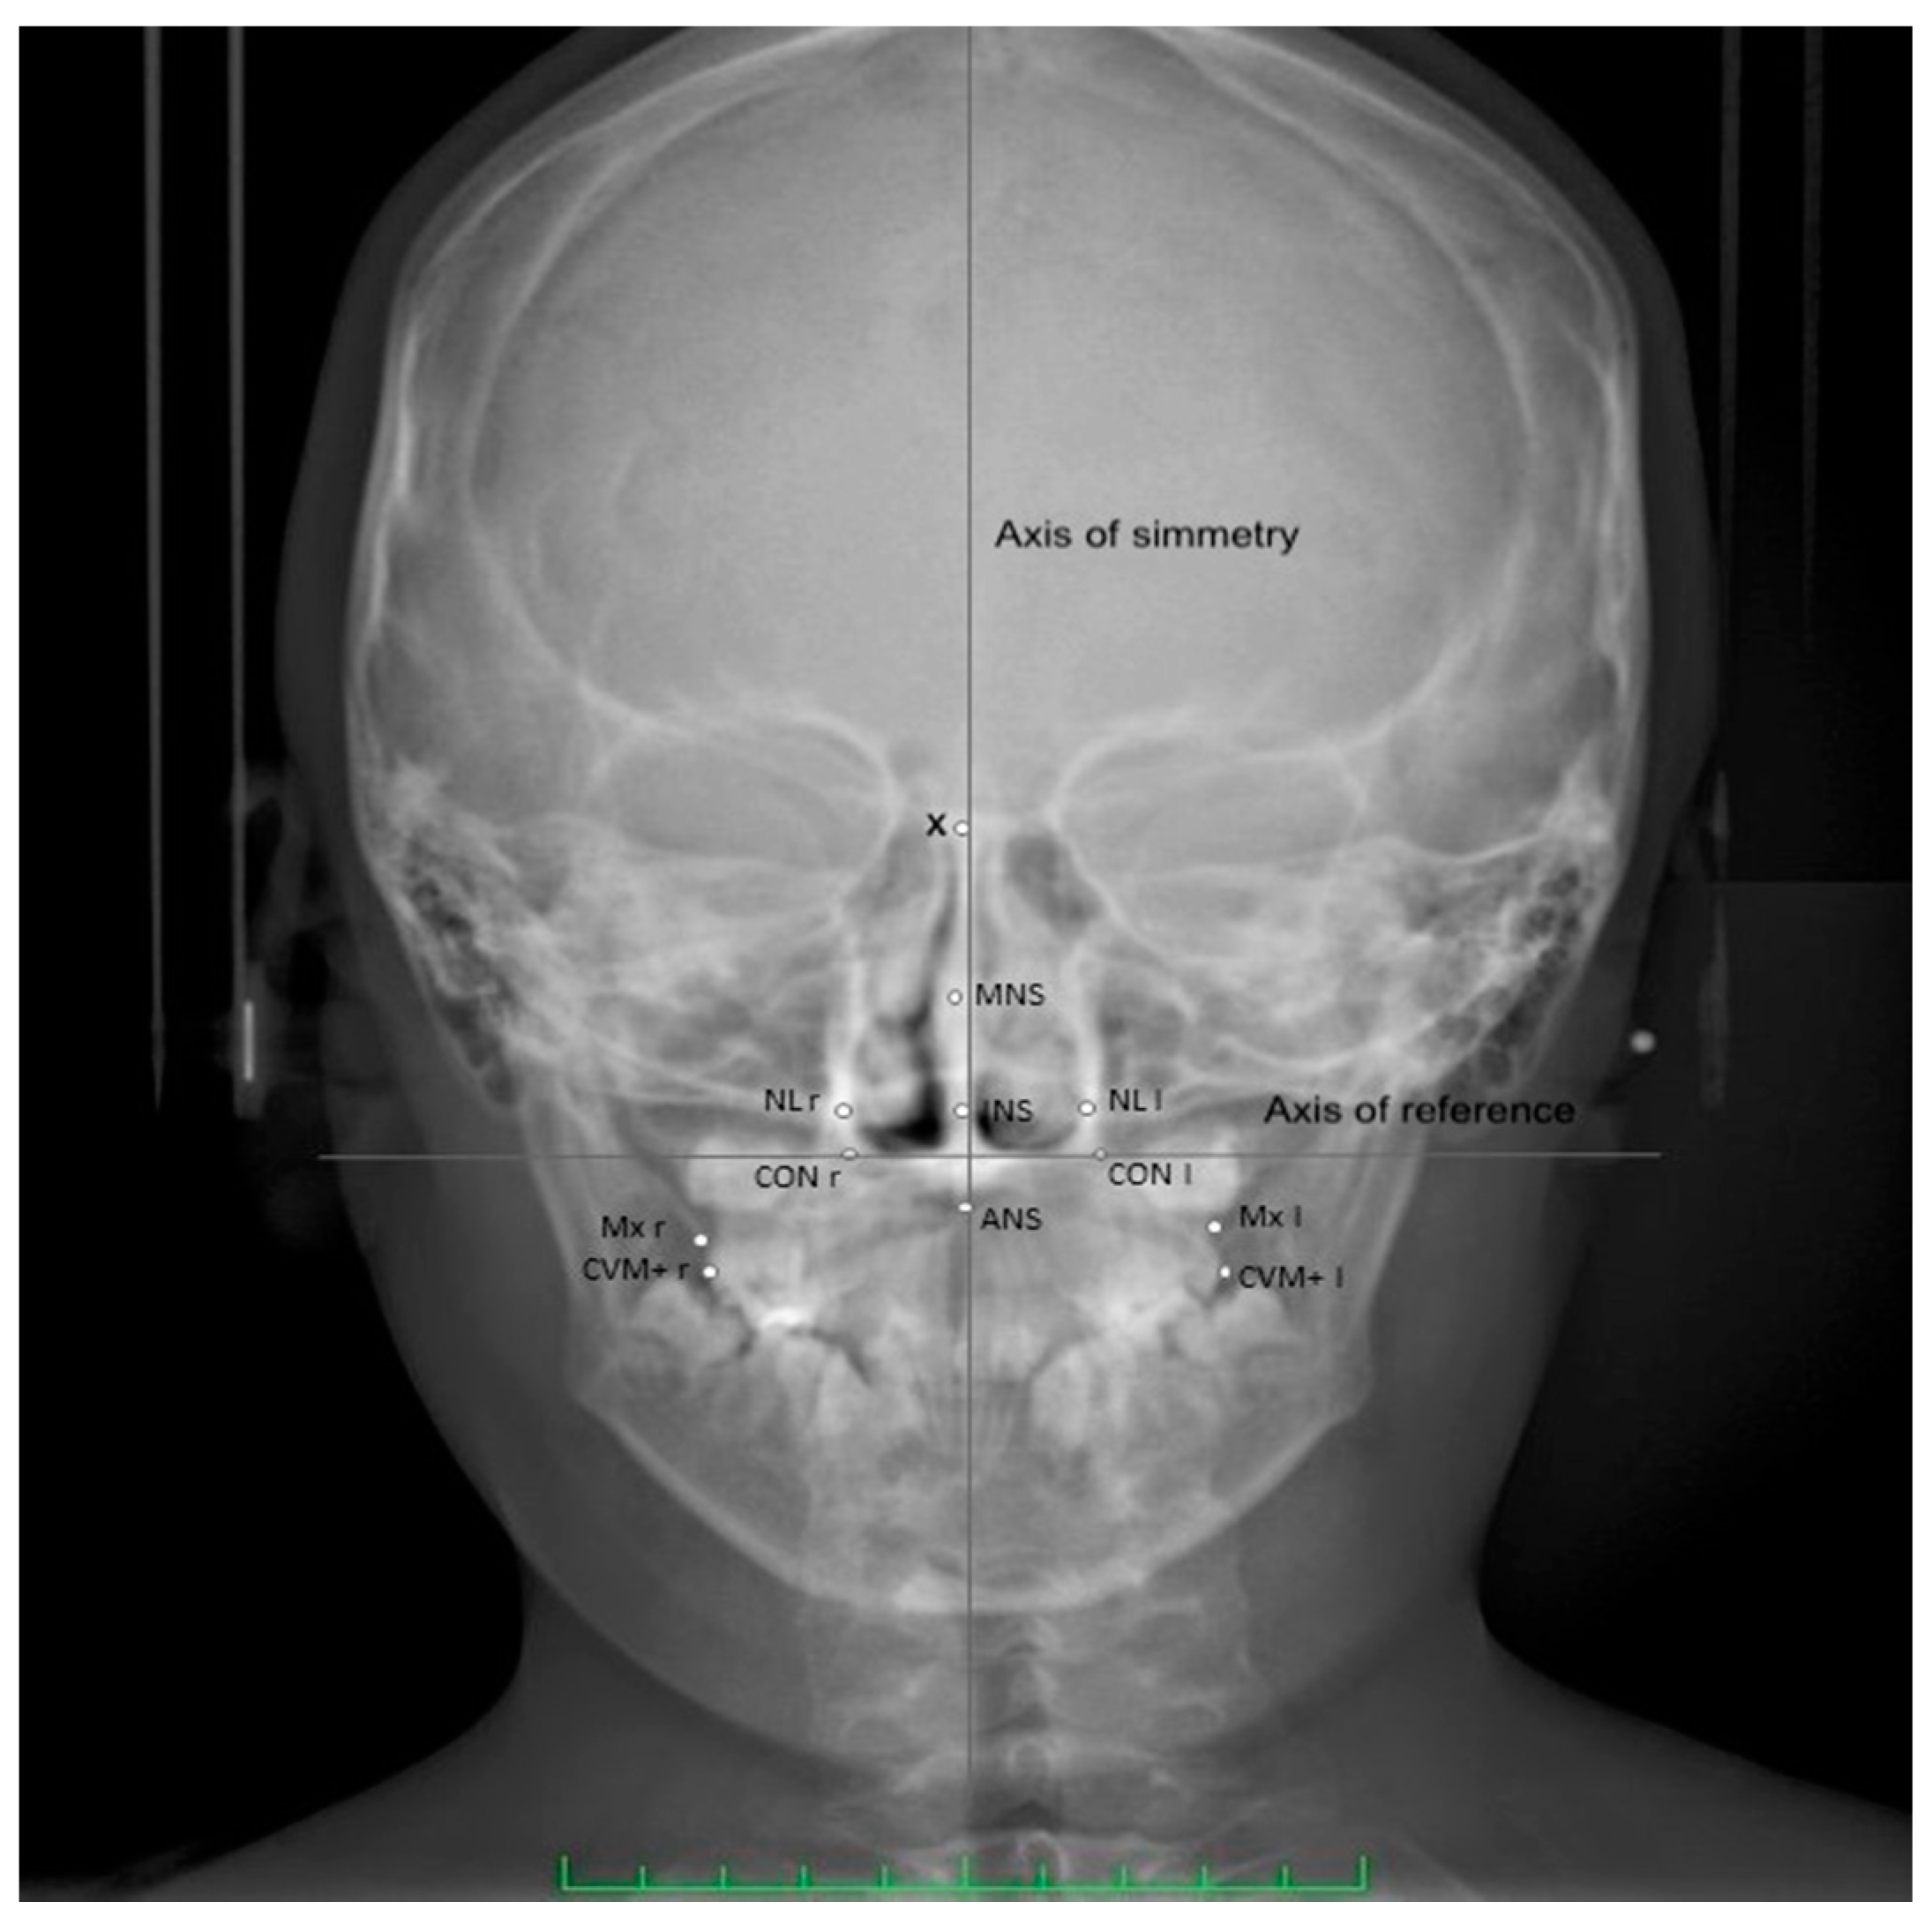

| Abbreviation | Definition |

|---|---|

| CVM+ l/r | Most prominent point on the sagittal plane of the vestibular-mesial cuspid-upper left and upper right first permanent molar (left and right) |

| MNS | Middle Nasal Septum-middle point of the maximal diameter of the medium third of nasal septum, on the horizontal plane |

| INS | Inferior part of the Nasal Septum-middle point of the maximal diameter of the inferior third of nasal septum, on the horizontal plane |

| MID | Crossing point between the axis of symmetry and the horizontal straight line that connects the homolog cephalometric points |

| CON | Point of cephalometric congruence between the inferior condyle of the occipital bone and the contour of the great occipital foramen |

| Axis of reference | Axis passing through right and left CON |

| Axis of symmetry | Perpendicular to the reference axis, passing through the highest point of the occipital foramen |

| NL | External points at the maximal horizontal diameter of nasal cavity, left and right |

| X | Crossing point between the perpendicular plate of the ethmoid and the projection of the floor of the anterior cranial fossa floor |

| ANS | Anterior cephalometric nasal spine |

| Mx l/r | The intersection of the lateral contour of the maxillary alveolar process and the lower contour of the maxillozygomatic process of the maxilla (left and right) |